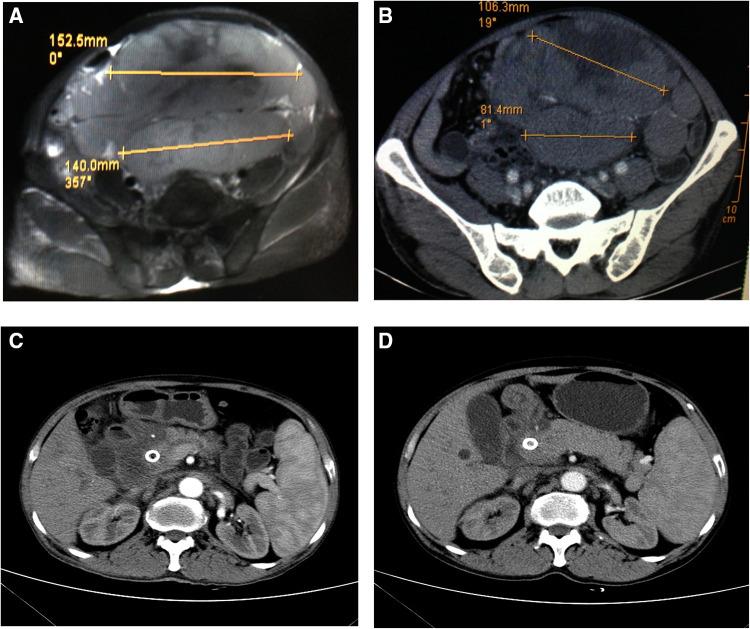

A 58-year-old male patient who had been undergoing chemotherapy for NHL was admitted to our institution for severe obstructive jaundice. The patient's hepatic function indicators were: alanine aminotransferase 211 U/L, aspartate aminotransferase 301 U/L, total bilirubin 485.6 μmol/L, and direct bilirubin 340.2 μmol/L. Abdominal magnetic resonance imaging showed massive lymphomatous lesions filling the peritoneal cavity. Magnetic resonance cholangiopancreatography revealed an external compressive stricture in the superior middle common bile duct and dilation of the intrahepatic and extrahepatic ducts. ERCP was performed unsuccessfully, due to the stricture at the descending junction of the duodenal bulb caused by lymphoma infiltration. So, EUS-guided anterograde common bile duct stenting the stomach was performed.

The patient's bilirubin level decreased significantly in the postoperative period, and no adverse reaction was observed. Computed tomography showed marked shrinking of the abdominal mass after targeted therapy.